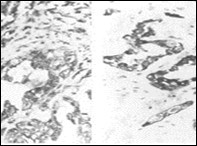

Figure 6.Parachordoma delineating clusters and nests of spindle-shaped and spherical, vacuolated cells with eosinophilic cytoplasm and uniform nuclei 16.

Figure 7.Parachordoma depicting immune reactivity to S100 protein 16.

Figure 8.Parachordoma demonstrating immune reactivity to vimentin 16.